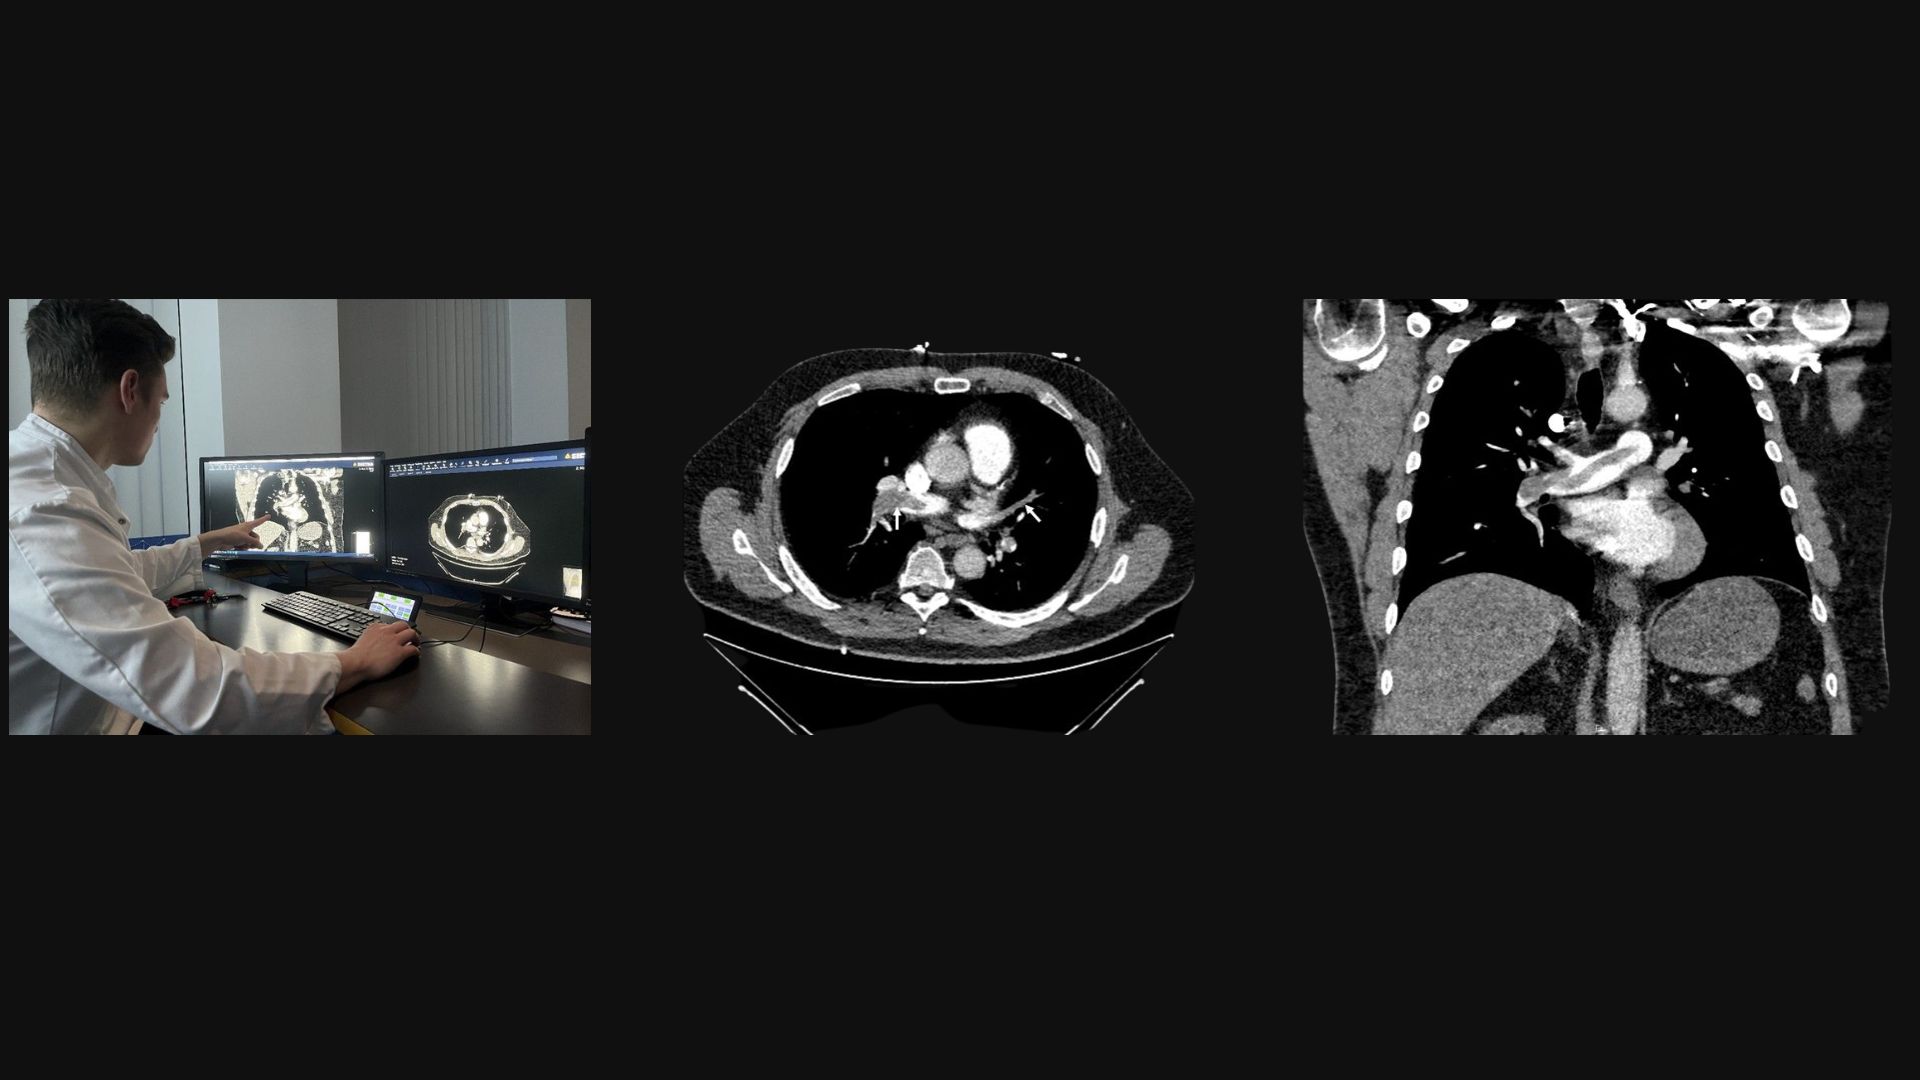

What you can see below in the images is our colleague Felix Busch analysing a saddle pulmonary embolism (PE) on a CT pulmonary angiography (CTPA).

Today, a 74-year-old patient arrived with sudden dyspnea, syncope, and chest pressure 11 days after knee surgery. CTPA shows a central “riding/saddle” thrombus (white arrows) straddling the bifurcation of the main pulmonary artery with extension into both main branches. Secondary signs of strain can include: RV/LV ratio (right ventricular (RV) to left ventricular (LV) ratio) > 1, septal bowing toward the LV, and mild reflux of contrast into the IVC (inferior vena cava).